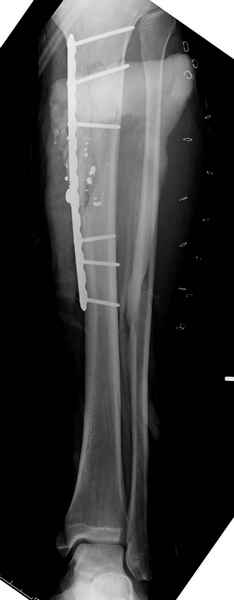

Здесь несколько примеров из нашей практики:

1 неполный перелом большеберцовой кости перкутанная пластина

При огнестрельных переломах ранами Первой и Второй степени по Gustilo при необходимости проводим как консервативную, так и оперативную методику лечения. Выбор метода фиксации всегда зависел от предпочтения специалиста, хотя в большинстве случаев преобладали накостные и интрамедуллярные методы.

В последующем, почти все случаи конвертировались во внутренние фиксаторы - пластины или интрамедуллярные. Исключения были в тех случаях, когда было невозможно добиться адекватной фиксации из-за локализации линии перелома, например, при низких экстраартикулярных переломах голени. Такие переломы фиксировали с помощью аппарата Илизарова и для стабильности вводили множество спиц в дистальном отделе.